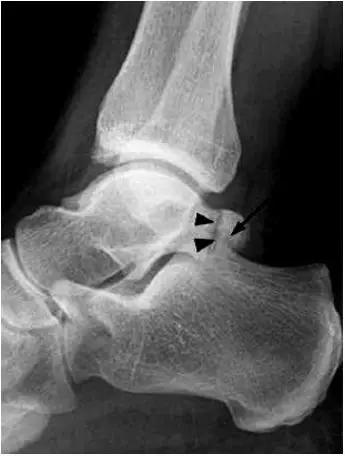

- 又称足球踝,通常为骨性撞击,由于经常性背屈导致胫骨远端关节面前缘与距骨颈部上缘骨赘反复撞击,有时滑膜软骨瘤病的游离体聚积在关节囊前部也会导致前撞击综合症。

- 放射学表现主要为胫骨前下缘与距骨颈部前上缘鸟嘴样骨刺形成。

放射学表现主要为胫骨前下缘与距骨颈部前上缘鸟嘴样骨刺形成

- Ⅰ度:滑膜撞击,X线片显示有炎性反应,骨刺大小为3mm;

- Ⅱ度:骨软骨反应性骨赘>3mm;

- Ⅲ度:严重的外生骨赘,可伴有或不伴有碎裂, 在距骨背侧可见继发性骨赘,常伴有骨赘的碎裂;

- Ⅳ度:距骨和胫骨关节骨性关节炎改变。